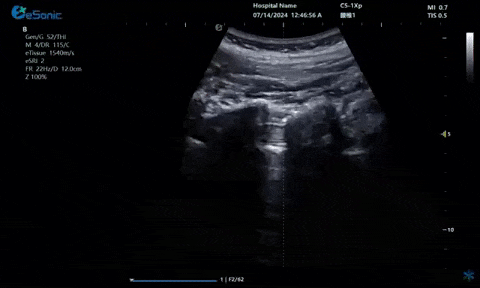

超声引导下肋间神经阻滞切面

9.1.gif